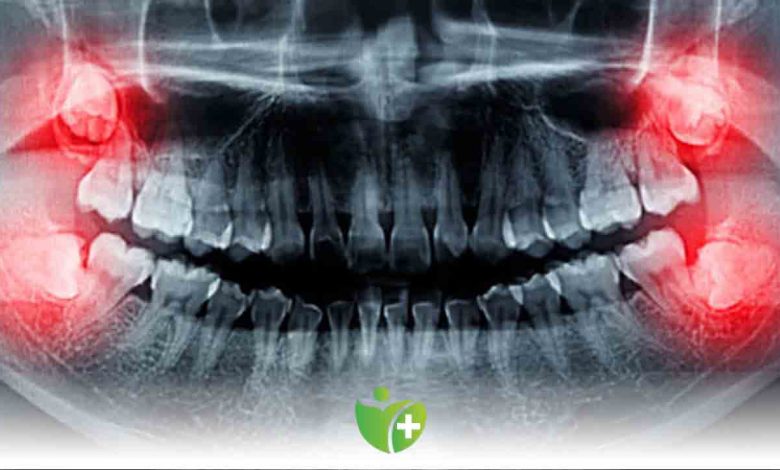

Çenemizin en sonunda bulunan ve 3. azı dişleri olan 20 yaş dişleri, 2 altta 2 de üstte olmak üzere ağızda 4 adet bulunuyor. Çenede yeterli yer varsa ve dişler ağızda doğru pozisyonu alabilmişse diş çekiminin gerekli olmadığını paylaşan Anadolu Sağlık Merkezi Ağız ve Diş Sağlığı Bölümü Klinik Koordinatörü Dt. Arzu Tekkeli, “20’lik dişler doğru bir diş fırçalama ile uzun yıllar sağlıkla ağzımızda durabilir” dedi.

20 yaş dişlerinin sürme döneminde hastanın şikayetlerinin hafiflemesi için ilaç kullanmak gerekebildiğini hatırlatan Ağız ve Diş Sağlığı Bölümü Klinik Koordinatörü Dt. Arzu Tekkeli, “Ağrı, ateş, yutma güçlüğü, lenfadenopati gelişmişse doktora başvurulması gerekir” diye konuştu. 20’lik dişler ağzın en arka bölgesinde olduğu için, bu duruma uygun diş fırçaları kullanılması gerektiğini hatırlatan Dt. Arzu Tekkeli, “20 yaş dişlerinin çürümesi, bu dişin önündeki dişi de çürüteceğinden böyle bir durumda hiç gecikmeden tam teşekküllü bir merkeze başvurulmalı. Bazı kişilerde 20 yaş dişi hiç çıkmayabilir, kemik içinde gömülü kalabilir. Böyle durumlarda hekiminiz dişin çekilmesine veya ağız içinde kalmasına muayene sonucu karar verir” açıklamasında bulundu